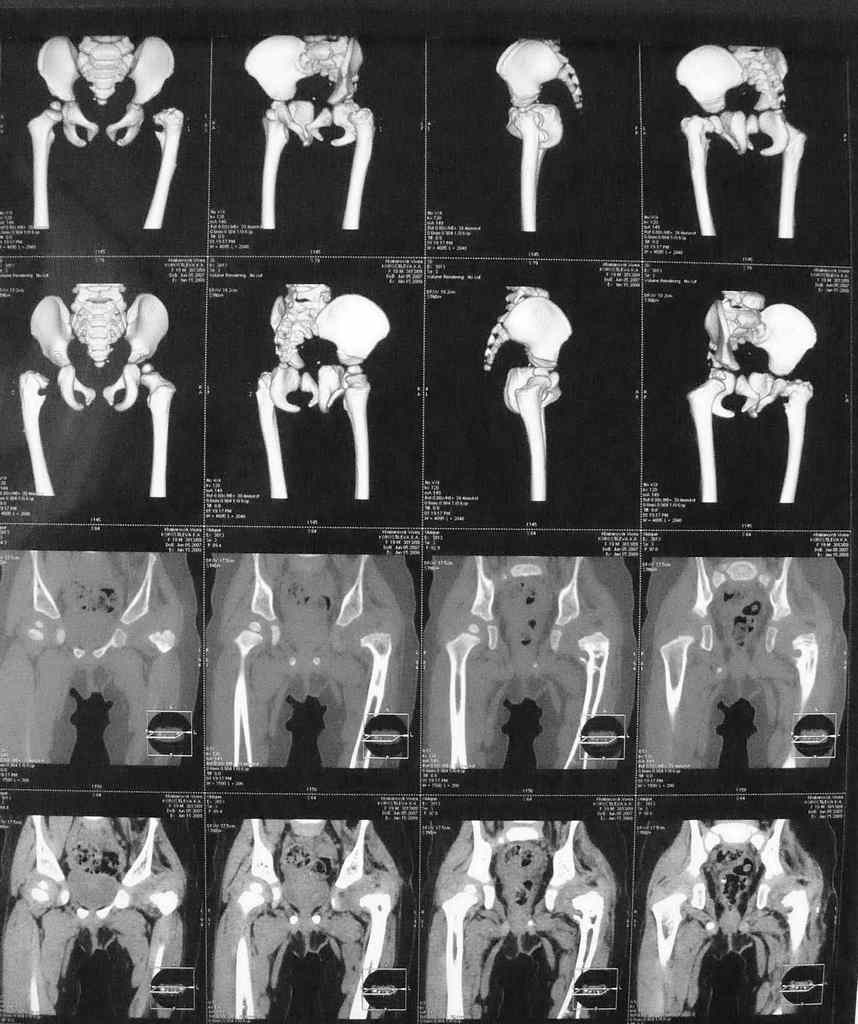

Уважаемые коллеги. Особенно детские ортопеды. Просит совета еще раз доктор Рыков из Хабаровска. У моей внучки 2 года ВВБ.

В 6 мес перенесла открытое вправление и деторсионную остеотомию с фиксацией.

Через 9 мес фиксатор удален. Предлагается следующее вмешательство в обьеме варизирующей остеотомии. В прищепке КТ и 3Д реконструкция.

Помогите советом кто в состоянии. Заранее благодарен. А Рыков